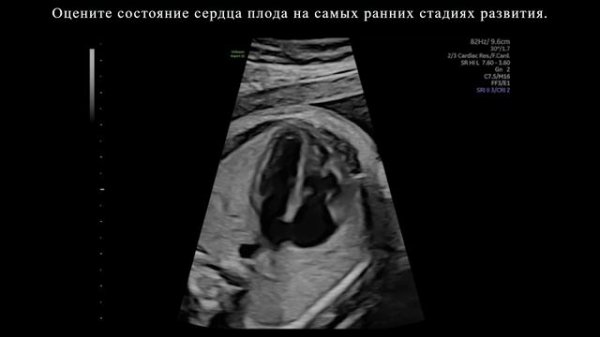

Обнаружение. Сердце плода на ультразвуковой системе Voluson Expert 22